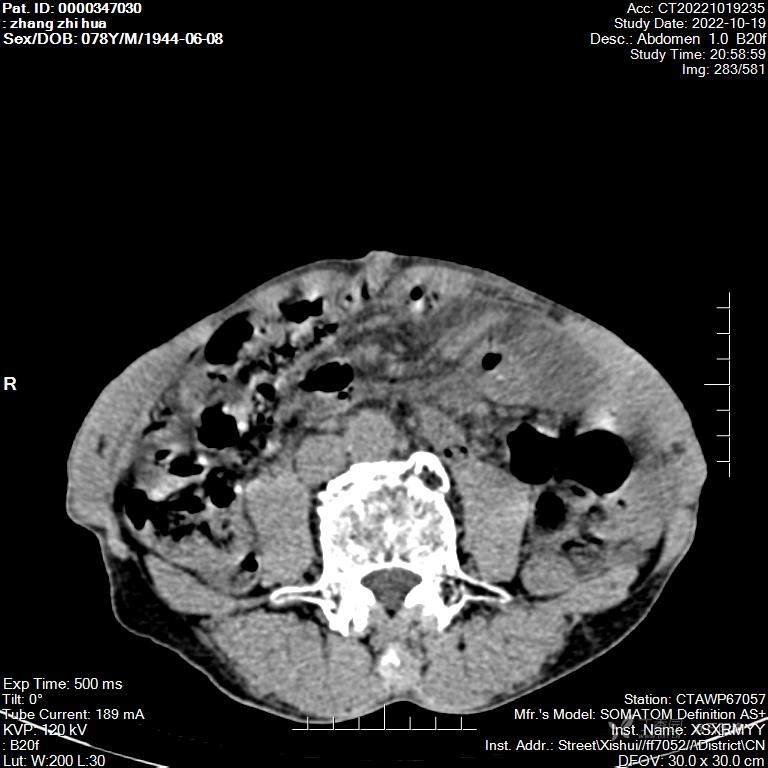

病例2:患者,男,78岁。因“腹痛2天,加重4小时”于2022.10.19入院。 既往于2019.2.14在我院因胃癌行根治性全胃切除术。查体:BP150 / 88 mmHg、HR 52次/分、R 20次/分、T 36.5 ℃腹膨隆,全腹压痛,伴反跳痛,肝脾肋下未及,双肾区无叩击痛,肠鸣音正常2022-10-19 CT平扫 1、胃术后可能,请结合病史。2、腹腔部分血管走形呈旋涡状,腹盆腔局部脂肪间隙模糊,请结合临床。3、少量盆腔积液。4、腹腔多发肠管扩张积气、积液。5、左侧腹股沟疝。入院后予禁食禁水,持续胃肠减压,解痉,抗感染治疗并积极做术前准备,并急诊行剖腹探查术,手术时之发现:腹腔如全胃切除伴胃空肠Roux-en-Y吻合术术后所见,全小肠系膜呈乳白色并肥厚,全小肠自食管空肠吻合口后方疝入并形成扭转。术中行腹内疝松解还纳术+修补术。术后第7天顺利出院。

第二例患者CT视频(上传在第一例患者上了)